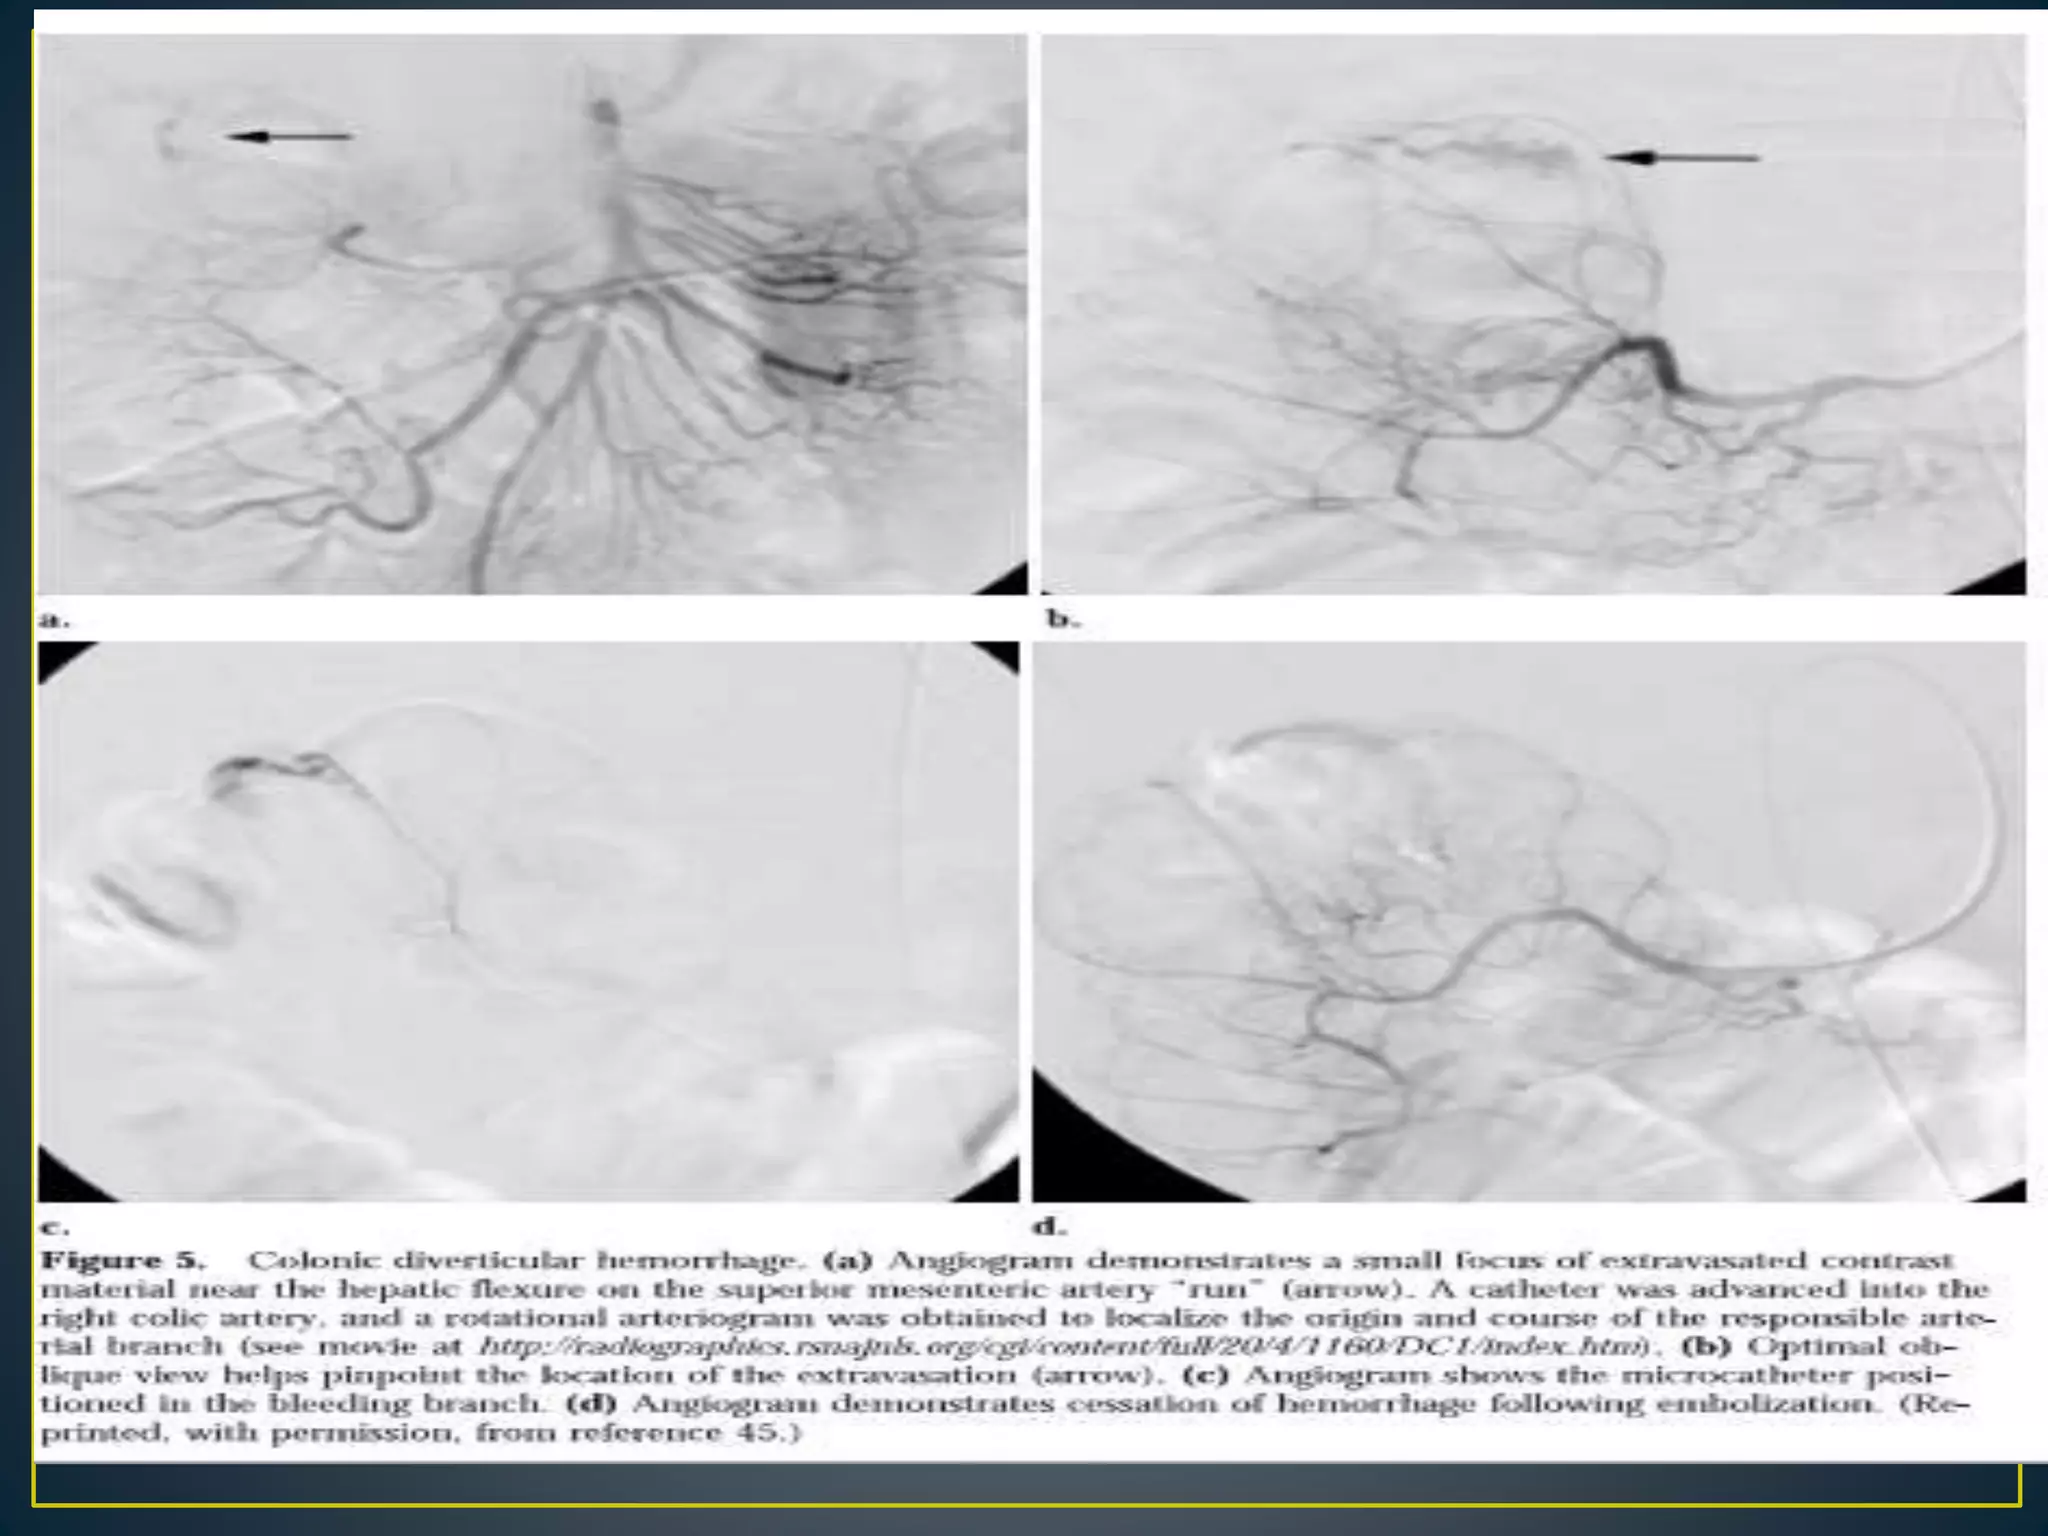

• Diverticulosis Has been implicated as the source of

bleeding in as many as 60% of cases of lower GI

bleeding.

• The diverticula are more prevalent in the left or sigmoid

colon, but positive arteriography findings for bleeding

localizes the bleeding to the right colon in 60% of cases

• Diverticular bleeding does not have a characteristic

appearance unless contrast fills the diverticulum itself

• The goal of embolotherapy is to stop blood flow to the

bleeding artery while maintaining viability of the

bowel.

• For many years, embolization, particularly in the small

intestine and colon, was avoided by angiographers

because of the fear of bowel infarction.

• However, with the development of coaxial

microcatheters (which can be negotiated directly to the

site of bleeding) and newer embolic agents (e.g.,

microcoils, polyvinyl alcohol [PVA] particles), the risk of

significant bowel ischemia is minimal.

• Embolotherapy has the advantage of immediate and

theoretically permanent cessation of bleeding without

the risks of vasopressin infusion or prolonged

catheterization

• For these reasons, the procedure has become

widely popular as first-line therapy for acute

gastrointestinal hemarrhage.